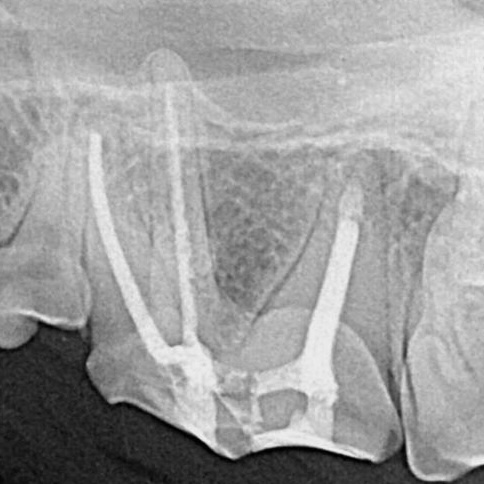

Endodontic

Save damaged or infected teeth with advanced root canal and pulp therapy designed to relieve pain and preserve your pet’s natural smile.